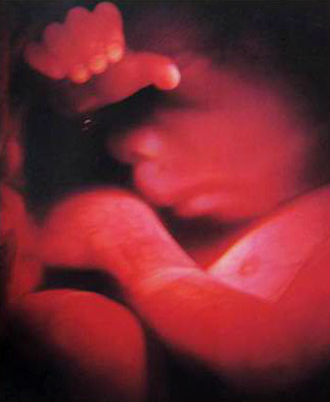

- 중기 정밀 초음파

(태아 내부장기 및 근골격 기형 등을 검사)